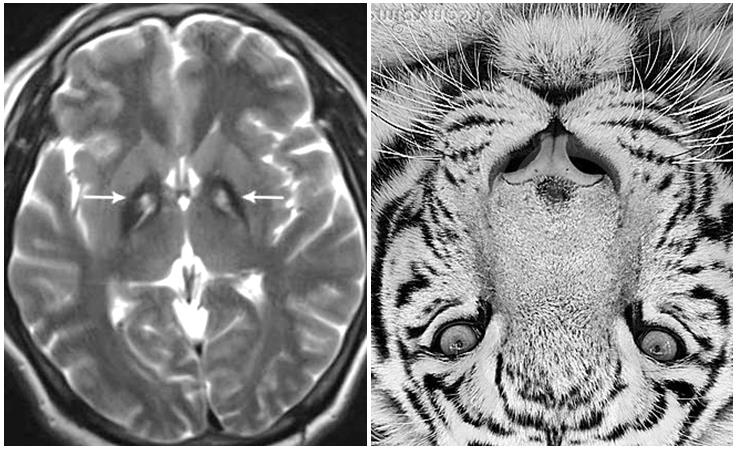

La neurodegeneración asociada a pantotenato quinasa, neurodegeneración por acumulación de hierro tipo 1, o síndrome de Hallervorden-Spatz es una entidad neurológica con herencia autosómica recesiva que aparece desde la infancia. Clínicamente se caracteriza por la presencia de demencia, alteraciones de la postura y el tono muscular, síntomas extrapiramidales y ataxia. Se debe a una mutación del gen que codifica la proteína pantotenato kinasa (PANK2), lo que da lugar a un acumulo de hierro en los ganglios basales y que da una imagen característica de “ojos de tigre” en Resonancia Magnética.